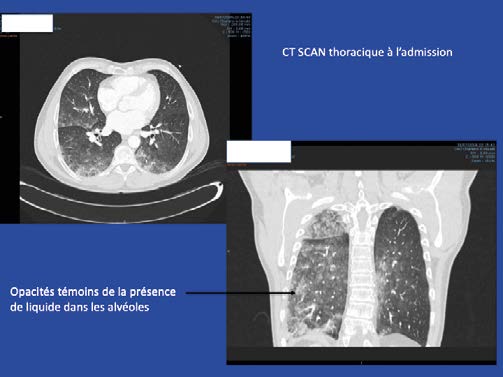

L’OPI se définit par la présence de liquide dans l’alvéole suite à la rupture de la barrière alvéolo-capillaire, ce qui empêche l’oxygénation normale de l’organisme. L’OPI touche principalement les sujets âgés de plus de 45 ans et hypertendus, mais survient aussi chez des sujets jeunes avec un coeur sain.

- Le gradient de pression transmurale (gradient entre la pression ca-pillaire et la pression alvéolaire) s’élève et la perméabilité de la barrière alvéolo-capillaire augmente avec transsudation de liquide dans les alvéoles. C’est l’oedème pulmonaire alvéolaire.

- Lorsque la pression transmurale s’élève au-delà du seuil de résis-tance de la barrière alvéolocapillaire , les lésions peuvent aller jusqu’à la rupture de la membrane avec saignements.